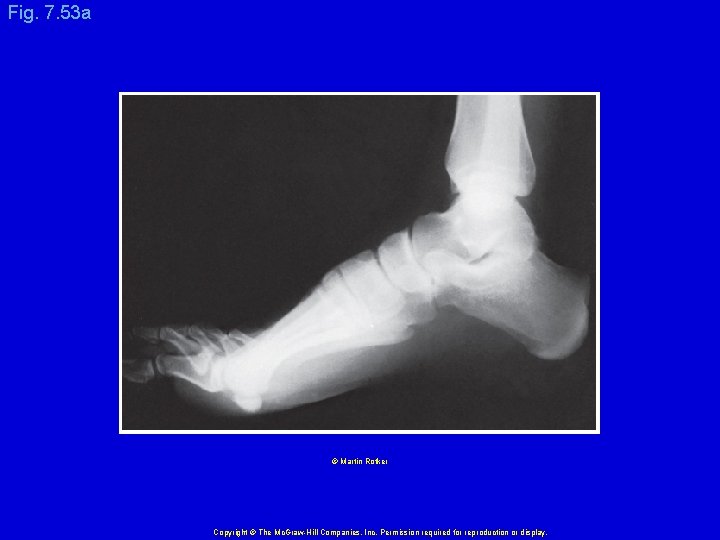

Fig. 7. 53 a © Martin Rotker Copyright © The Mc. Graw-Hill Companies, Inc. Permission required for reproduction or display.

Fig. 7. 53 b Right Foot Tibia Fibula Talus Navicular Medial cuneiform Calcaneus Calcaneal tuberosity Phalanges Metatarsals (metatarsus) Tarsals (tarsus) Copyright © The Mc. Graw-Hill Companies, Inc. Permission required for reproduction or display.